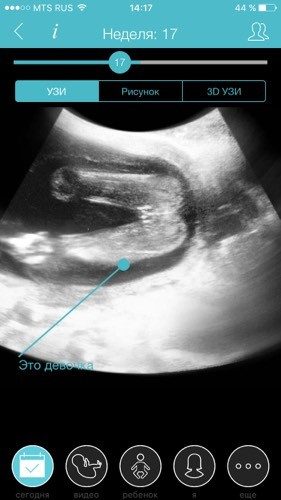

Узи девочка или мальчик: Мальчик или девочка? На каком сроке узнают пол ребенка?

На 21 неделе на УЗИ уже отчетливо можно различить мальчик это или девочка, потому что половые органы сформированы практически полностью. Вероятность правильного определения пола почти стопроцентная. Конечно, исследование должно проводиться на современной аппаратуре, а врач обладать необходимым опытом и квалификацией.

УЗИ на пол ребенка предполагает неинвазивную визуализацию наружных половых органов плода. На основании этого делается вывод о половой принадлежности.

Если врач УЗД видит на экране мошонку и пенис, то плод наиболее вероятно является мальчиком, а если определяются половые губы – то скорее всего в утробе девочка.

После проведения ультразвуковой диагностики пациентке выдается протокол обследования, в котором отображается срок беременности и пол ребенка (основанный на визуализации наружных половых органов).

К протоколу обследования могут прикладываться распечатанные снимки, на которых видно наличие пениса или половых губ.

Точность ультразвукового определения пола плода составляет 90-95%. В некоторых случаях с помощью ультразвука определить пол плода не удается, т.к. плод занимает «неудобное» для визуализации положение, половые органы могут быть закрыты пуповиной или же на них наслаивается изображение плаценты.